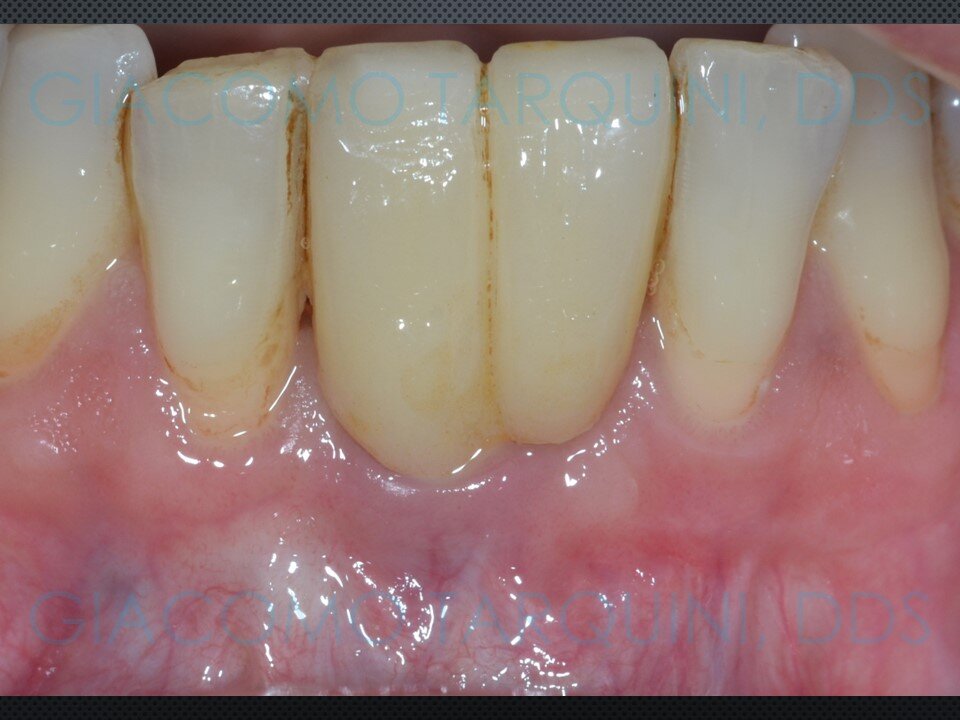

- Rientro chirurgico e follow-up radiografico per valutare il grado di rigenerazione ossea ottenuta

La decontaminazione della superficie implantare con il dispositivo “Piezoclean by Dr. Giacomo Tarquini”, combinata con il protocollo noto come “Poncho technique”, consente una ricostruzione prevedibile del tessuto osseo attorno a un impianto affetto da perimplantite. Questo approccio comporta una significativa semplificazione delle fasi chirurgiche e una bassa morbidità operatoria, riducendo al contempo in modo sostanziale i tempi complessivi della riabilitazione.

Ho aggiornato il caso clinico con ricostruzione Panorex + sondaggi parodontali pre e post-operatori.